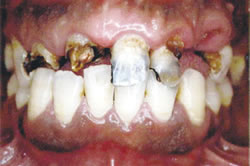

| 派遣切りされた30代のレントゲン 重度の虫歯多数、下の歯はほとんど歯根しか残っていない。愛知で派遣切りされ、故郷に戻った。無料低額診療事業を利用して治療に。 |